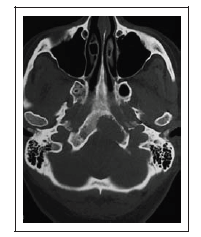

Uma mulher de 44 anos de idade passou a apresentar, na última semana, episódios esporádicos de parestesias em hemiface esquerda. Por duas vezes, apresentou dificuldade para ingerir líquidos. Apresentou três episódios de vertigens rotatórias e vômitos. De patologias pregressas, apenas hipertensão arterial leve, controlada com uso de losartana. O exame neurológico é normal. Não há alterações objetivas no exame nos nervos cranianos. Hemograma, glicemia, dosagem de derivados nitrogenados, eletrólitos no sangue: tudo normal. Exame de neuroimagem, reproduzido a seguir, mostra a presença de uma lesão expansiva osteolítica no terço inferior do clivus, à esquerda, que se estende até o arco anterior do atlas.

Nesse caso, o acesso que permite ressecção da lesão associada a um menor risco de morbidade e menor tempo de internação hospitalar é a via